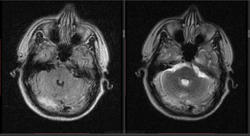

Мужчина 1964 г.р. Жалобы на нарушение памяти, снижение зрения и кратковременную потерю сознания, температура нормальная.

Я думаю что это может быть какой нибудь васкулит, либо Posterior Reversible Encephalopathy Syndrome, о чем можно думать в данном случае?

eto pres

Я представлял синдром с более выраженным изменением сигнала от белого вещества и меньшим - коры.